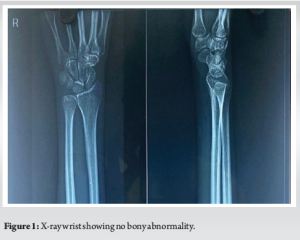

A 44-year-old male presented with complaints of pain and swelling over the volar aspect of his right wrist that had persisted for the past 2 months. The pain had started earlier than the swelling. The pain was insidious in onset and gradual in progression and was moderate-to-severe in intensity. It is aggravated with passive and active movements of the wrist and metacarpophalangeal (MCP) joints. The patient was unable to make a fist, resulting in weakness of grip, which led to difficulty in performing activities of daily living. There was no history of involvement of any other small or large joints of the body. There was no history of morning stiffness, fever, weight loss, or night cries. On examination, local temperature was raised, and diffuse tenderness was present over the swelling. The skin was normal and not adherent to underlying structures. A full range of extension was present in the MCP, proximal interphalangeal, and distal interphalangeal joints, but flexion of these movements was limited. Laboratory investigations revealed raised C-reactive protein and erythrocyte sedimentation rate, whereas the total leukocyte count remained within normal limits at 6800/µL. Rheumatoid factor and anti-cyclic citrullinated peptide (CCP) antibodies were negative. Basic imaging in the form of a plain X-ray of the wrist (Fig. 1) showed no abnormalities. Given the persistent swelling and non-specific laboratory findings, a high-resolution ultrasound of the wrist was performed. The ultrasound demonstrated a heterogeneous hypoechoic collection with thickening of the tendon sheath along the flexor pollicis longus (FPL) tendon, as well as flattening of the median nerve within the carpal tunnel, suggesting possible compressive tenosynovitis. Based on the above findings, a differential diagnosis of TB and GCT of the flexor sheath was made. The differential diagnosis of RA was not kept as there were no signs or symptoms suggestive of RA, and also the anti-CCP antibody and RA factors were negative. To further evaluate the extent and nature of the lesion, a contrast-enhanced magnetic resonance imaging (MRI) of the wrist was done. It showed tenosynovitis of the flexor tendons with marked synovial enhancement of the wrist joint, suggestive of an inflammatory aetiology (Fig. 2a and b). Based on the imaging and persistent symptoms, a surgical approach was planned for both diagnostic and therapeutic purposes. The patient underwent an open exploration of the wrist through a volar approach (Fig. 3).